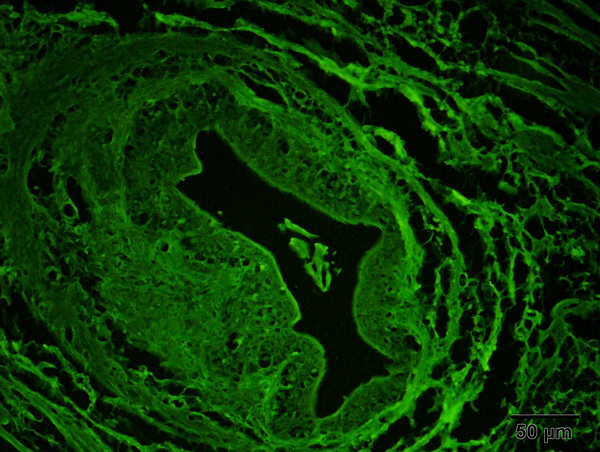

Ovary